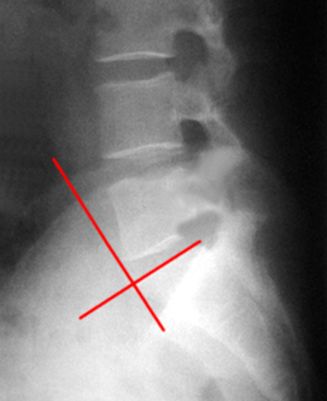

图6-6 椎斜位DR平片

1 上关节突 superior articular process 2 关节突关节 zygapophyseal joint

3 椎弓峡部 isthmus of vertebral arch 4 椎间孔 foramen intervertebrale

5 下关节突 inferior articular process 6 髂骨翼 ala of ilium

7 关节突关节 zygapophyseal joint 8 横突 transverse process

9 L2/3椎间隙 L2/3 lumber intervertebrale space

10 第2腰椎椎体 2nd lumbar vertebral body

11 椎弓根 vertebral pedicle